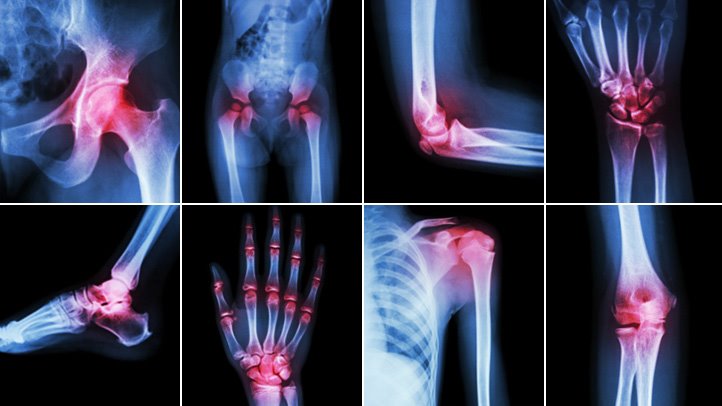

Виды артроза по локализации

Разные формы заболевания зависят от местоположения пораженного сустава. Наименее тяжелой считается плечевая форма. Артроз может проявляться в следующих областях:

- шейный отдел;

- коленный сустав (затрагивает обе ноги, степень выраженности может различаться);

- голеностопный сустав;

- тазобедренный сустав (часто встречается у пожилых людей).